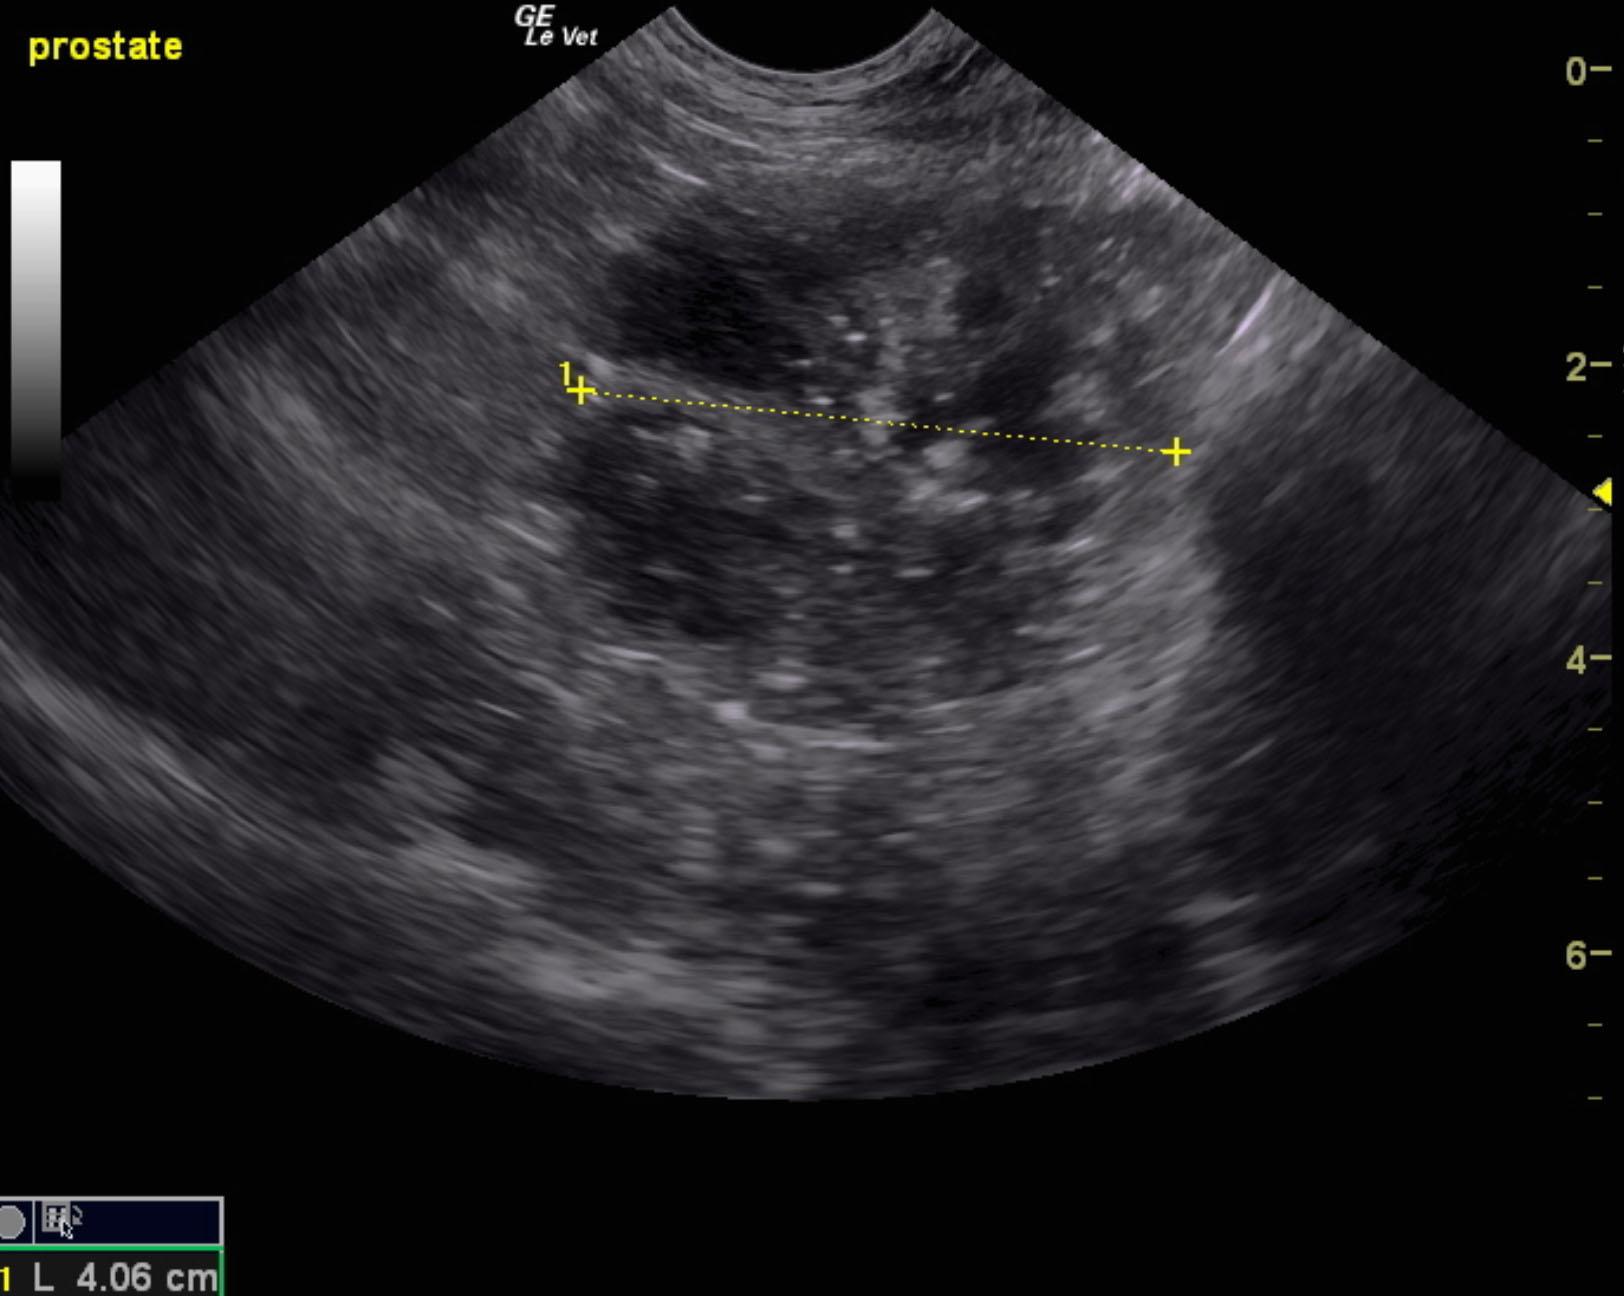

An 8-year-old neutered male mixed breed dog with a history of pollakiuria, stranguria, and weight loss. The dog was presented for evaluation of tenesmus, diarrhea, and hematuria. Physical examination and rectal palpation were within normal limits.